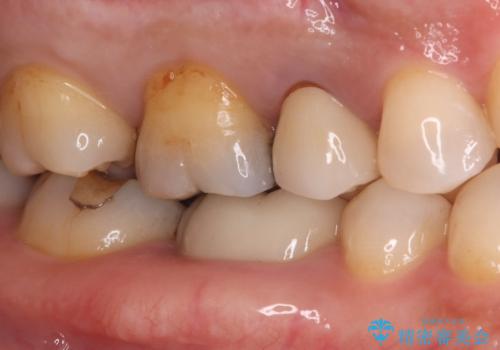

銀歯からセラミックへ。右上奥歯の精密根管治療と審美修復